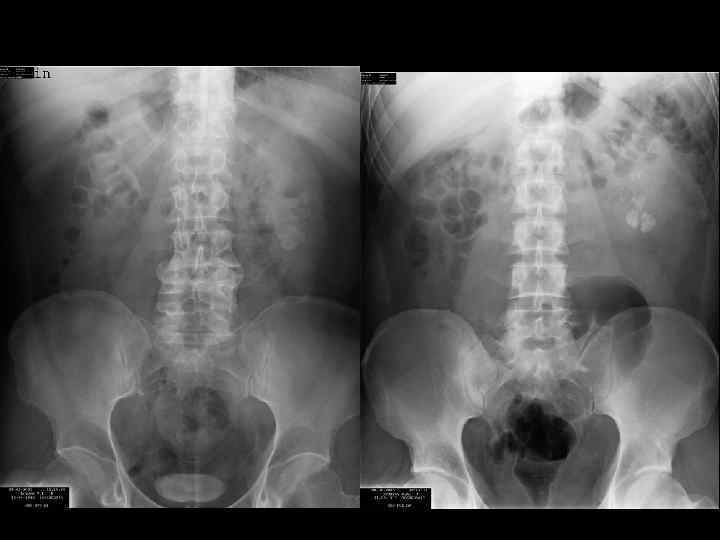

Больной А.